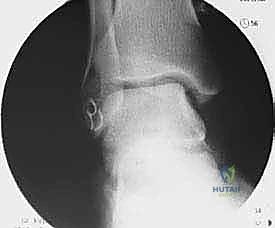

التشريح الدقيق للكاحل: فهم بنية الأربطة الجانبية

لفهم طبيعة الإجراء الجراحي، يجب أولاً فهم التشريح المعقد للكاحل. يتكون مفصل الكاحل من التقاء ثلاثة عظام: الظنبوب (القصبة)، الشظية، وعظم الكاحل (Talus). لضمان ثبات هذا المفصل أثناء الحركة، يتم دعمه بشبكة قوية من الأربطة.

الأربطة الجانبية (الموجودة في الجزء الخارجي من الكاحل) هي الأكثر عرضة للإصابة، وتتكون من ثلاثة أربطة رئيسية:

- الرباط الكاحلي الشظوي الأمامي (ATFL): هو أضعف الأربطة الجانبية والأكثر تمزقاً أثناء التواء الكاحل للداخل (Inversion).

- الرباط العقبي الشظوي (CFL): رباط قوي يساعد في استقرار الكاحل والمفصل تحت الكاحل. يتمزق عادة في الإصابات الأكثر شدة.

- الرباط الكاحلي الشظوي الخلفي (PTFL): هو الأقوى ونادراً ما يتمزق إلا في حالات الخلع الكامل للكاحل.

عندما تتمزق هذه الأربطة ولا تلتئم بشكل صحيح، تصبح رخوة وضعيفة. هذا التراخي يؤدي إلى حركة غير طبيعية لعظم الكاحل داخل المفصل، مما يسبب احتكاكاً مفرطاً وتآكلاً لغضروف المفصل بمرور الوقت.

2. التدخل الجراحي (متى يكون ضرورياً؟)

إذا استمرت الأعراض لأكثر من 3 إلى 6 أشهر رغم الالتزام التام بالعلاج التحفظي، وإذا أظهرت أشعة الرنين المغناطيسي (MRI) تمزقاً كاملاً أو تآكلاً شديداً في الأربطة، يصبح التدخل الجراحي هو الحل الوحيد لمنع تلف غضاريف الكاحل والإصابة بالخشونة المبكرة.